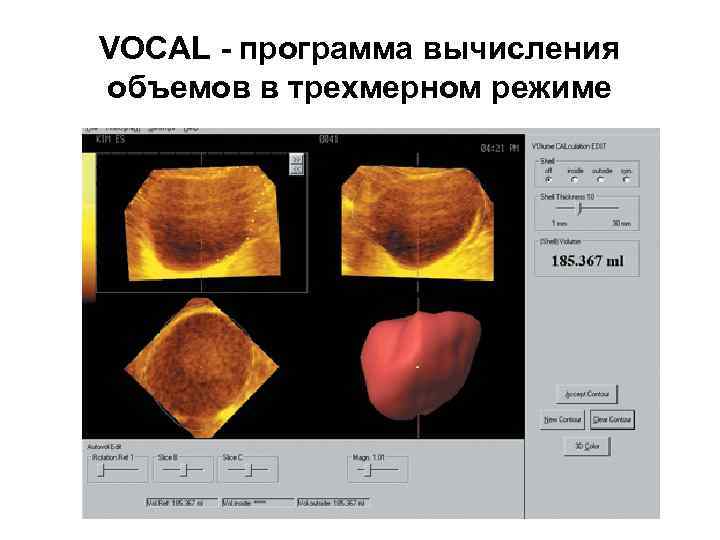

VOCAL - программа вычисления объемов в трехмерном режиме

VOCAL - программа вычисления объемов в трехмерном режиме